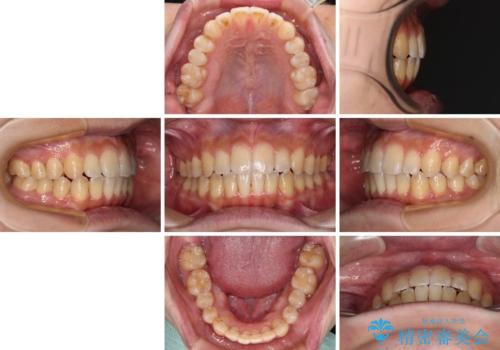

オープンバイトと目立つ銀歯 インビザライン矯正とセラミック修復治療

銀歯のセラミック治療が1番の希望であったため、ここまで歯列がきれいに整うとは思ってなかったようで、大変喜んでいただけました。